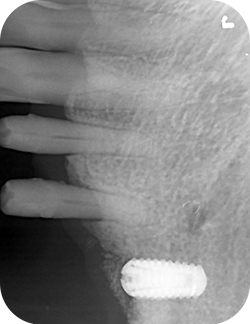

RIOScan offers various functions to minimize work time. Users can place RIOScan at any small space in their clinics, such as chair side, worktable or x-ray room, for convenient scanning.

Outstanding Digital Imaging Plate System

High-definition image quality